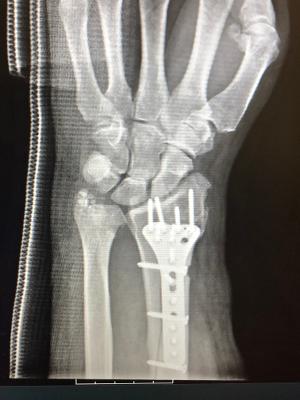

Helmet didn't help in my crash but at least I could tell the wife I was wearing it. Broken leg and wrist, six hours of surgery, plates and screws, 7 days in the hospital, hit max out of pocket on my insurance of $6500.00 12 weeks in a wheelchair (two more to go) hopefully can begin walking mid October. Helmets might not always help but they don't hurt. Wife wants the bike sold but not sure thats going to happen. People still drive cars after accidents. Only going about 15 MPH got caught in the groove between concrete drive and asphalt road and went down hard.

Attachments

• hand.jpg

hand.jpg

18 KB · Views: 245

• hand1.jpg

hand1.jpg

20.4 KB · Views: 261